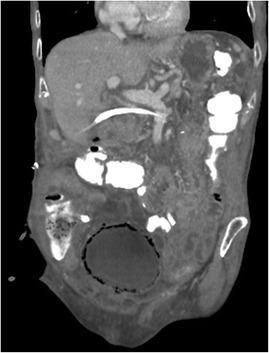

Emphysematous cystitis is a very rare complicated urinary tract infection characterized by air in the bladder wall.

We report two clinical cases of emphysematous cystitis of an 83-year-old Caucasian woman with diabetes mellitus and a 78-year-old Caucasian man with no past medical history. They presented with severe confusion and abdominal distension. Emphysematous cystitis was diagnosed in time with a thorough physical examination, urine analysis and computed tomography. The patients were successfully treated with antibiotic therapy and bladder drainage.